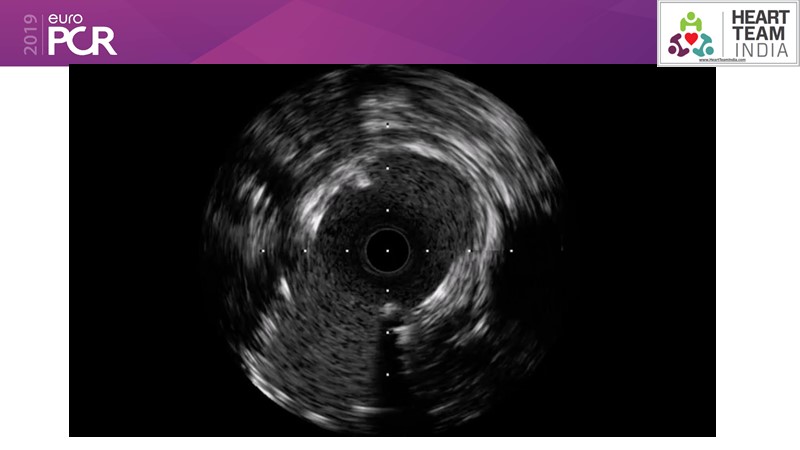

Ability to treat diabetic patients: DES + DCB strategy

Consult this session to get insights about the need for a dedicated drug eluting stent (DES), as well as the benefits of a DES+DCB strategy, for diabetes mellitus (DM) and acute MI (AMI) patients.

- To understand and discuss the need for a dedicated DES for diabetes mellitus (DM) and acute MI (AMI) patients

- To understand and learn benefits of DES+DCB strategy to provide uniform and homogenous drug delivery in patients with diabetes mellitus and acute MI